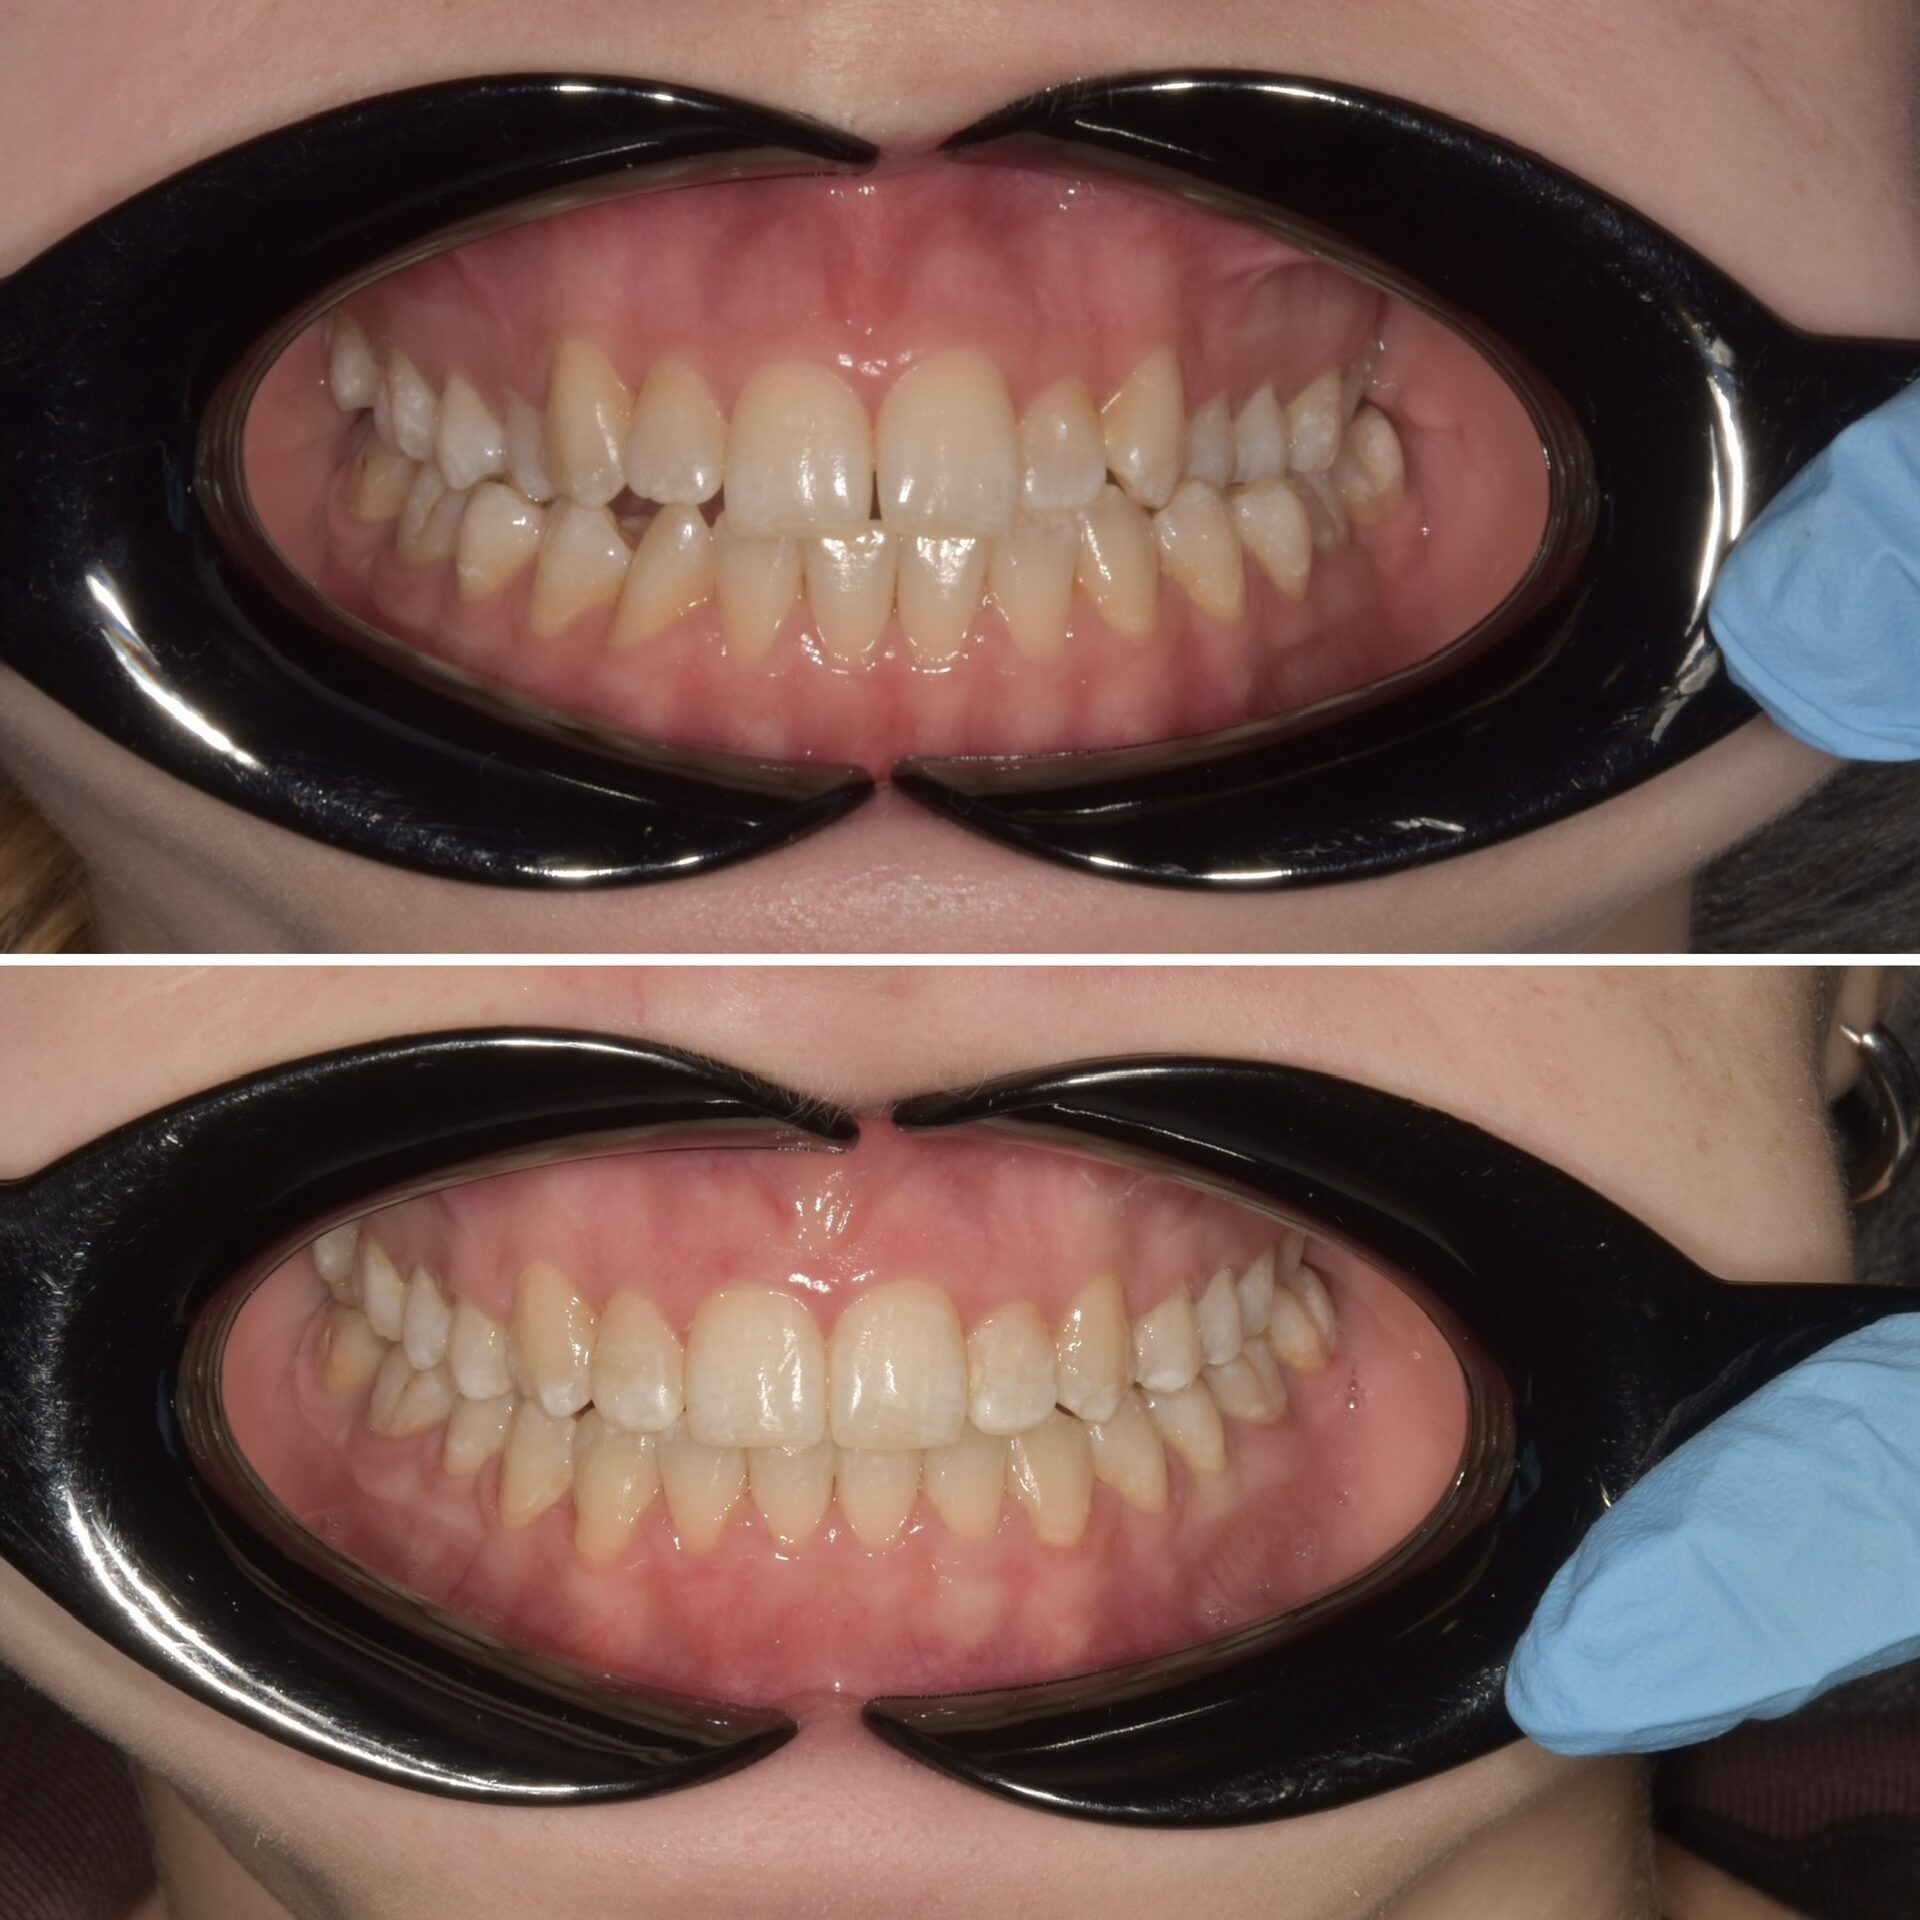

Виниры на своих зубах и коронки на имплантатах

Виниры на своих зубах и керамические коронки на имплантатах

Виниры на своих зубах,безметалловые коронки на имплантате